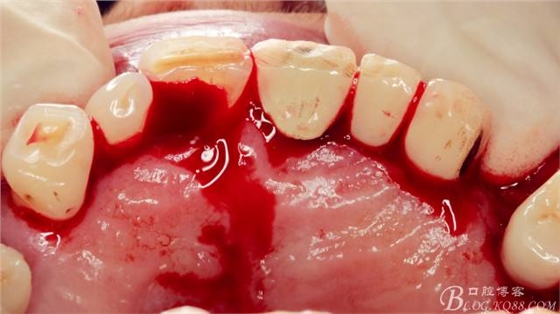

局麻下做齦溝內(nèi)切口

翻瓣,長柄球鉆清掃薄薄的骨皮質(zhì),暴露出牙冠,動(dòng)作一定要輕柔,感覺就像在雞毛撣子一樣撣花瓶上的灰一樣,因?yàn)楣呛脱烙再|(zhì)有明顯的密度差異,手感上面差別比較明顯。